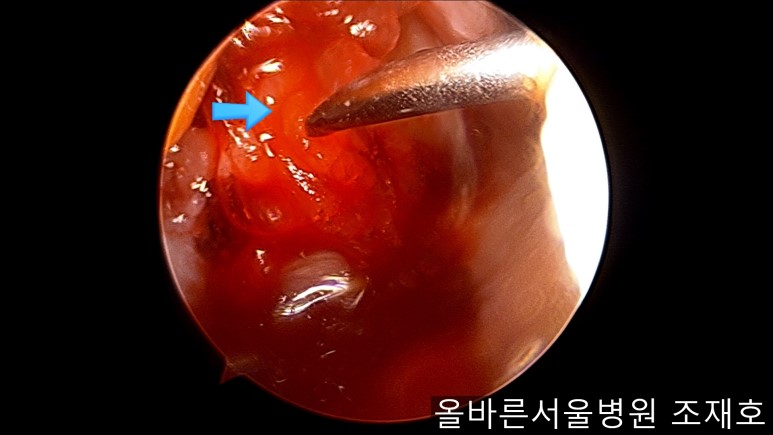

通过关节镜图像可看到:由于内侧股骨髁软骨损伤骨头已经显露出来。

image_9824311181519375935940.jpg

胫骨上端的软骨损伤严重,也露出了骨头。

image_9926851221519375935929.jpg

正是缺失软骨的部位碰到一起,引发剧烈疼痛,腿部逐渐变形。